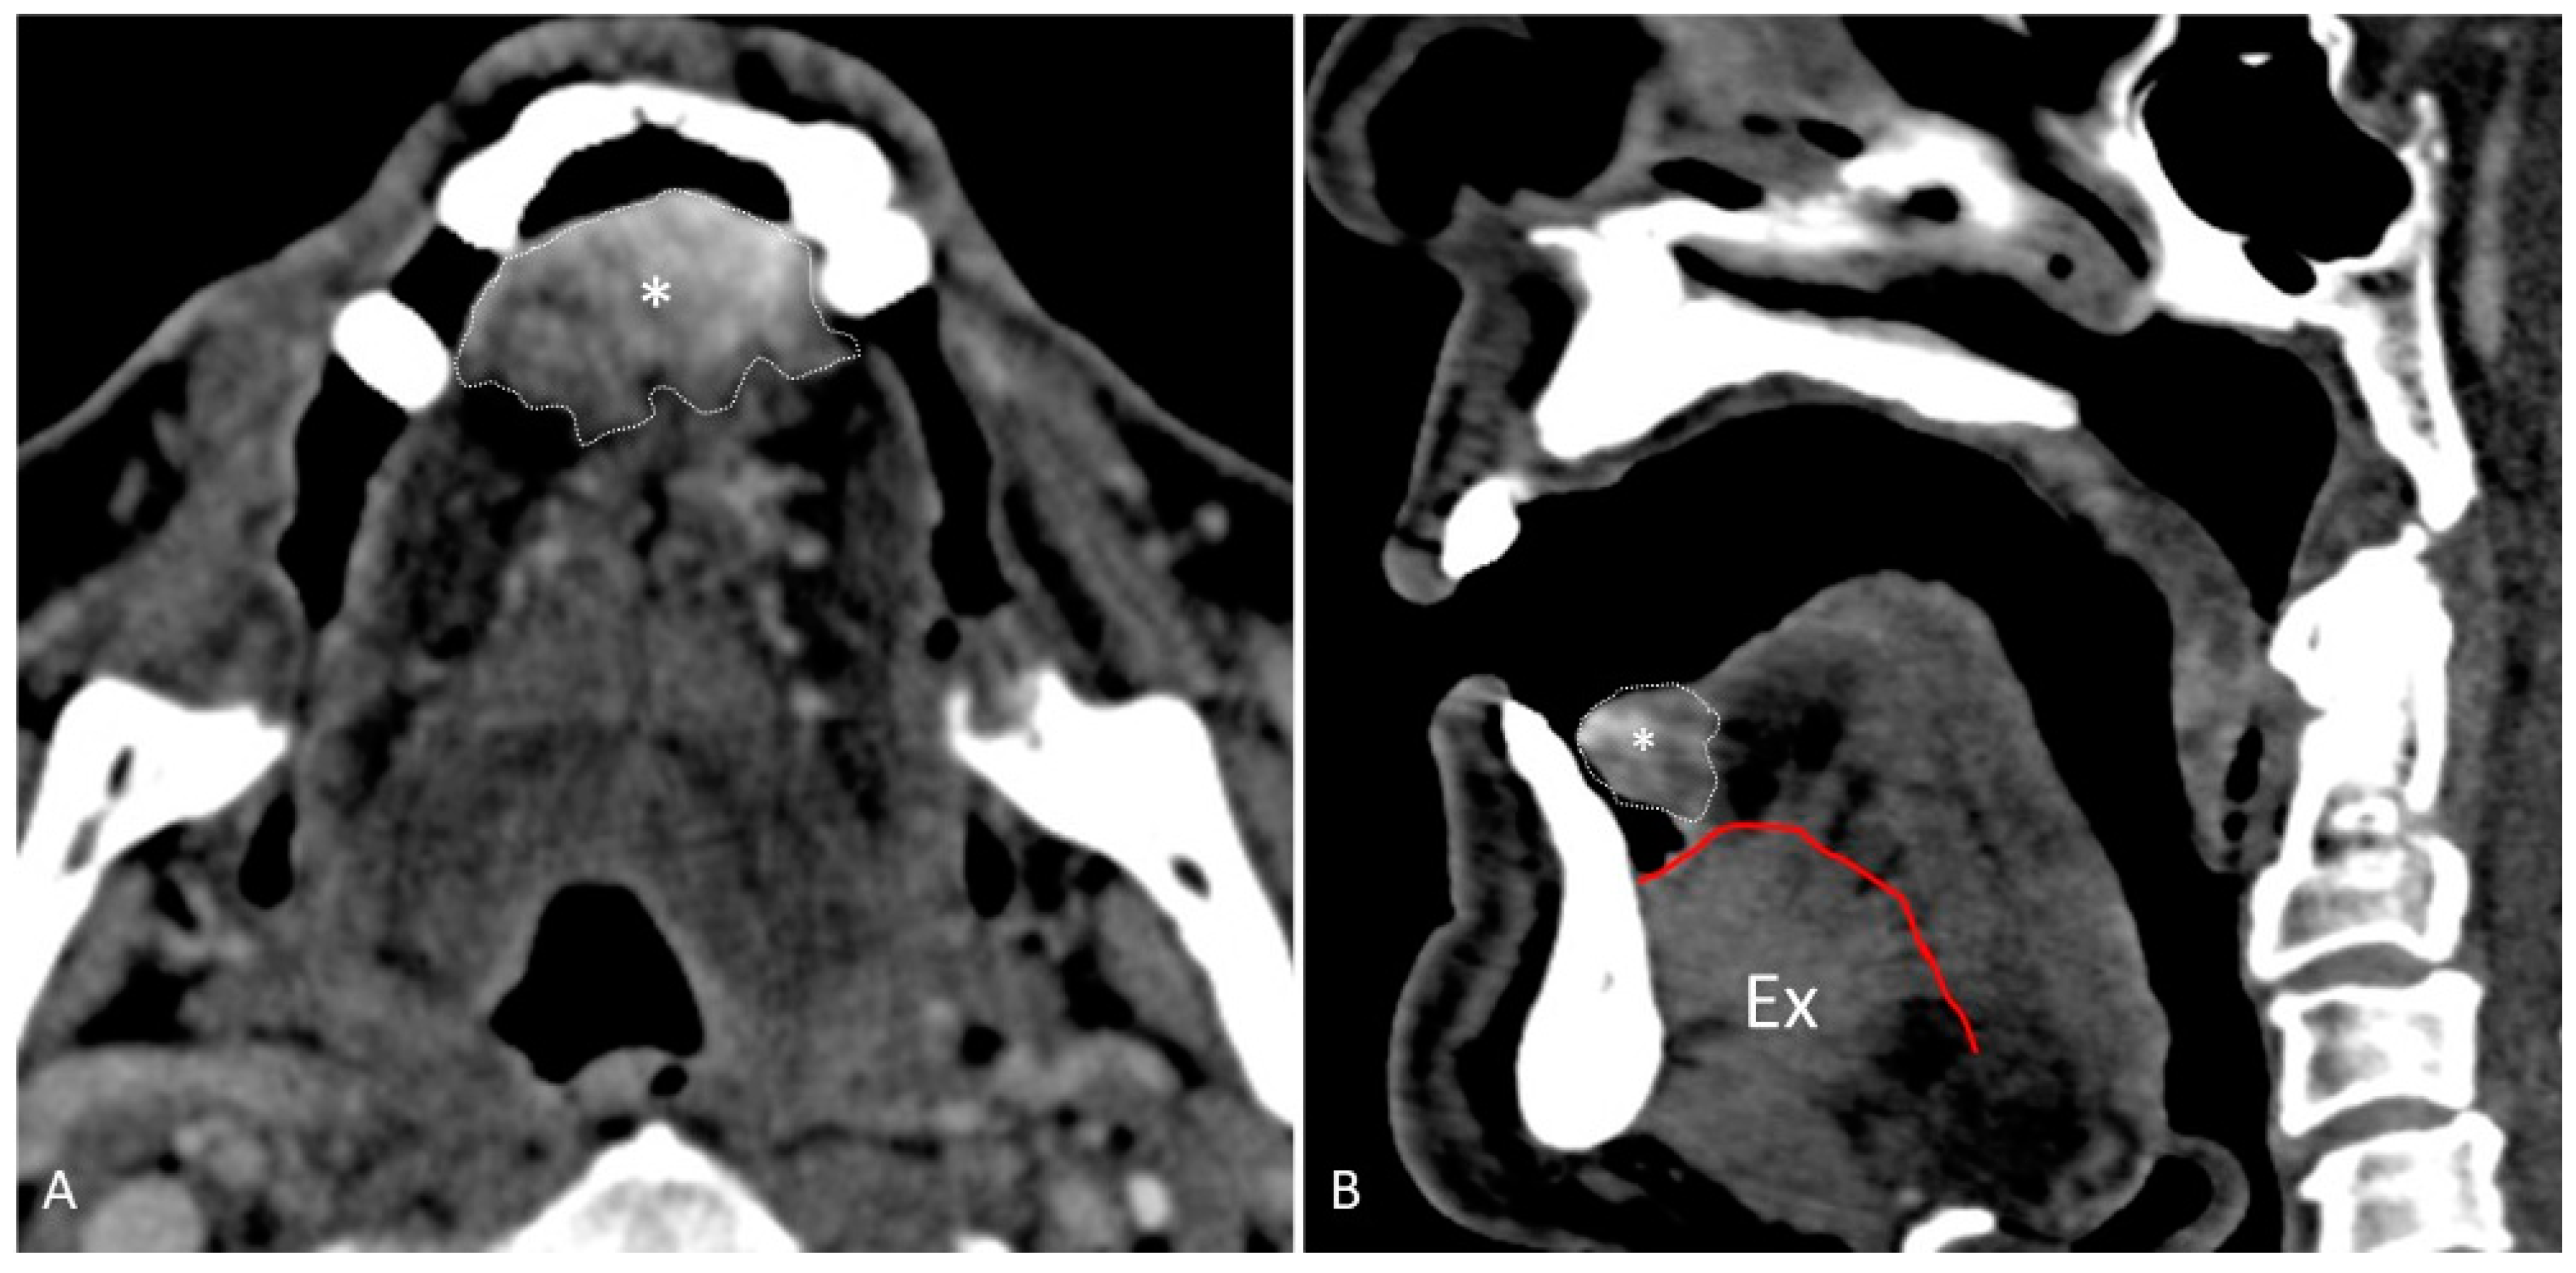

- Water distension of the oral vestibule. This technique is exclusively used on MRI examinations since MRI has a high contrast for liquids by using specific sequences, especially T2 sequences. Water distension of the oral vestibule is performed by asking patients to drink 20–40 mL of still water and keep it in the mouth for the time necessary to acquire the images (T2 and pre- and post-contrast T1 sequences) [47]. This manoeuvre distends the oral vestibule and the presence of water provides excellent natural contrast between the lesion and the adjacent mucosal surfaces (Figure 17).